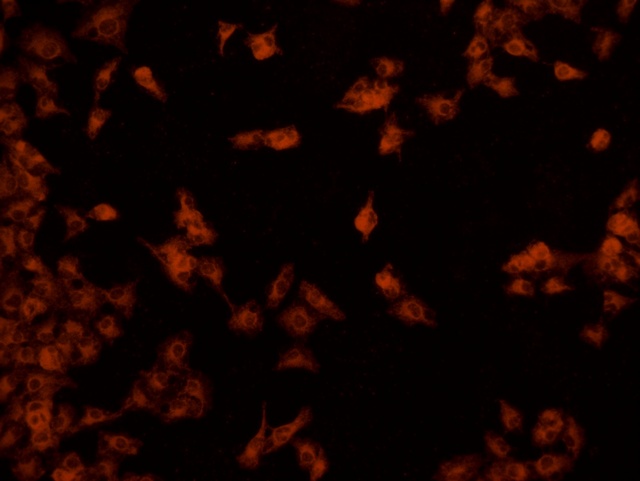

南華大學(xué)在生物醫(yī)學(xué)研究領(lǐng)域一直走在學(xué)術(shù)前沿,近日,該校引進(jìn)Mshot明美的倒置熒光顯微鏡MF52-N,搭配顯微鏡相機(jī)MSX2,為細(xì)胞切片標(biāo)本的研究提供了強(qiáng)大的技術(shù)支持,進(jìn)一步提升了科研實(shí)力。

MF52-N倒置熒光顯微鏡以其數(shù)顯LED熒光模塊和深度優(yōu)化的光路設(shè)計(jì),成為細(xì)胞切片觀察的理想選擇。其簡(jiǎn)單易用的熒光激發(fā)操作,大大降低了實(shí)驗(yàn)難度,提升了工作效率。同時(shí),該顯微鏡還能提供高質(zhì)量的相襯、熒光和明場(chǎng)成像,確保科研人員能夠捕捉到細(xì)胞切片的每一個(gè)細(xì)節(jié)。

在南華大學(xué)的實(shí)驗(yàn)室中,科研人員正借助這套先進(jìn)的顯微系統(tǒng),對(duì)細(xì)胞切片標(biāo)本進(jìn)行深入探索。

此外,MSX2顯微鏡相機(jī)的加入,更是如虎添翼。這款相機(jī)以其高分辨率和敏銳的圖像捕捉能力,記錄了實(shí)驗(yàn)過(guò)程中的每一個(gè)重要瞬間,為數(shù)據(jù)分析與論文發(fā)表提供了有力支持。